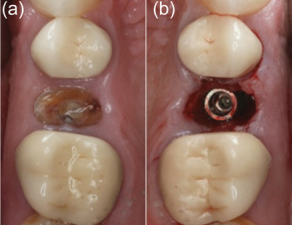

Minimally invasive removal of fractured premolar and placement of immediate implant (Megagen Anyridge) without osteotomy on Patient 3: (a) Fractured non‐restorable premolar. (b) Prepless immediate implant. (c) Cover screw placed to accommodate grafting with cortical cancellous allograft. (d) Anatomical healing abutment placed on the day of surgery. (e) Final monolithic Zr restoration. (f) Peri‐apical radiograph of day of surgery with anatomical healing abutment. (g) Peri‐apical radiograph with definitive restoration at 12 months.